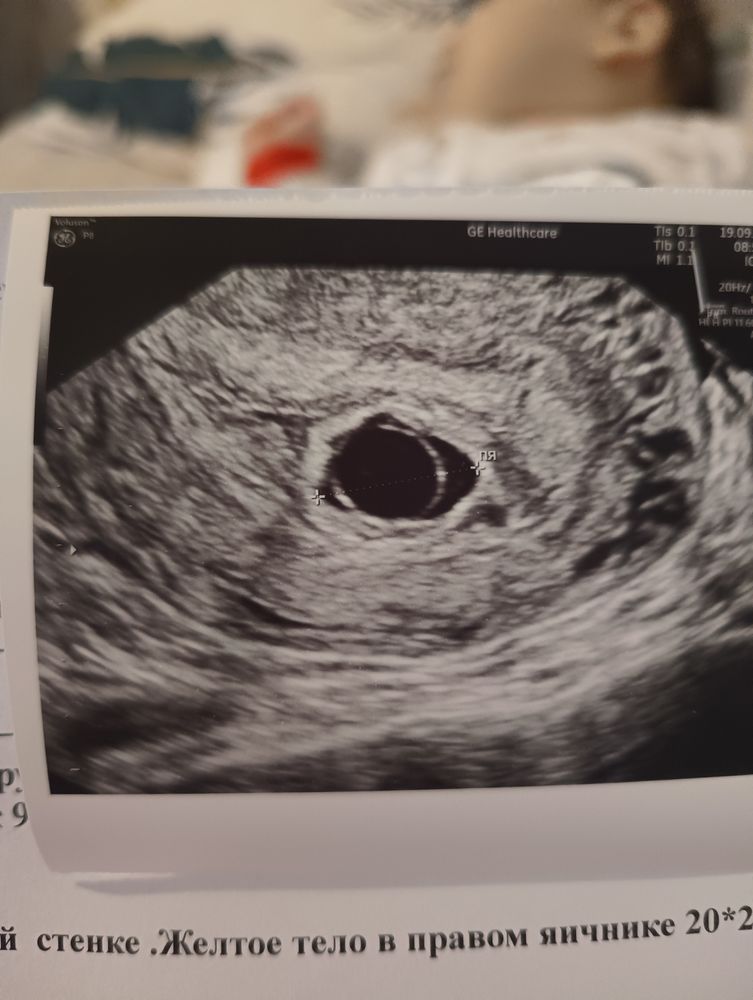

по овуляции срок 6,5 по узи 5,5

неделю назад когда пя был 11.7 врач сказала что все в матке есть и даже пульсацию поймала 70-80ударов, но сказала прийти через неделю тогда точно можно сердце услышаьь

а сегодня пя18,5 но пя пустое, как это возможно я не понимаю